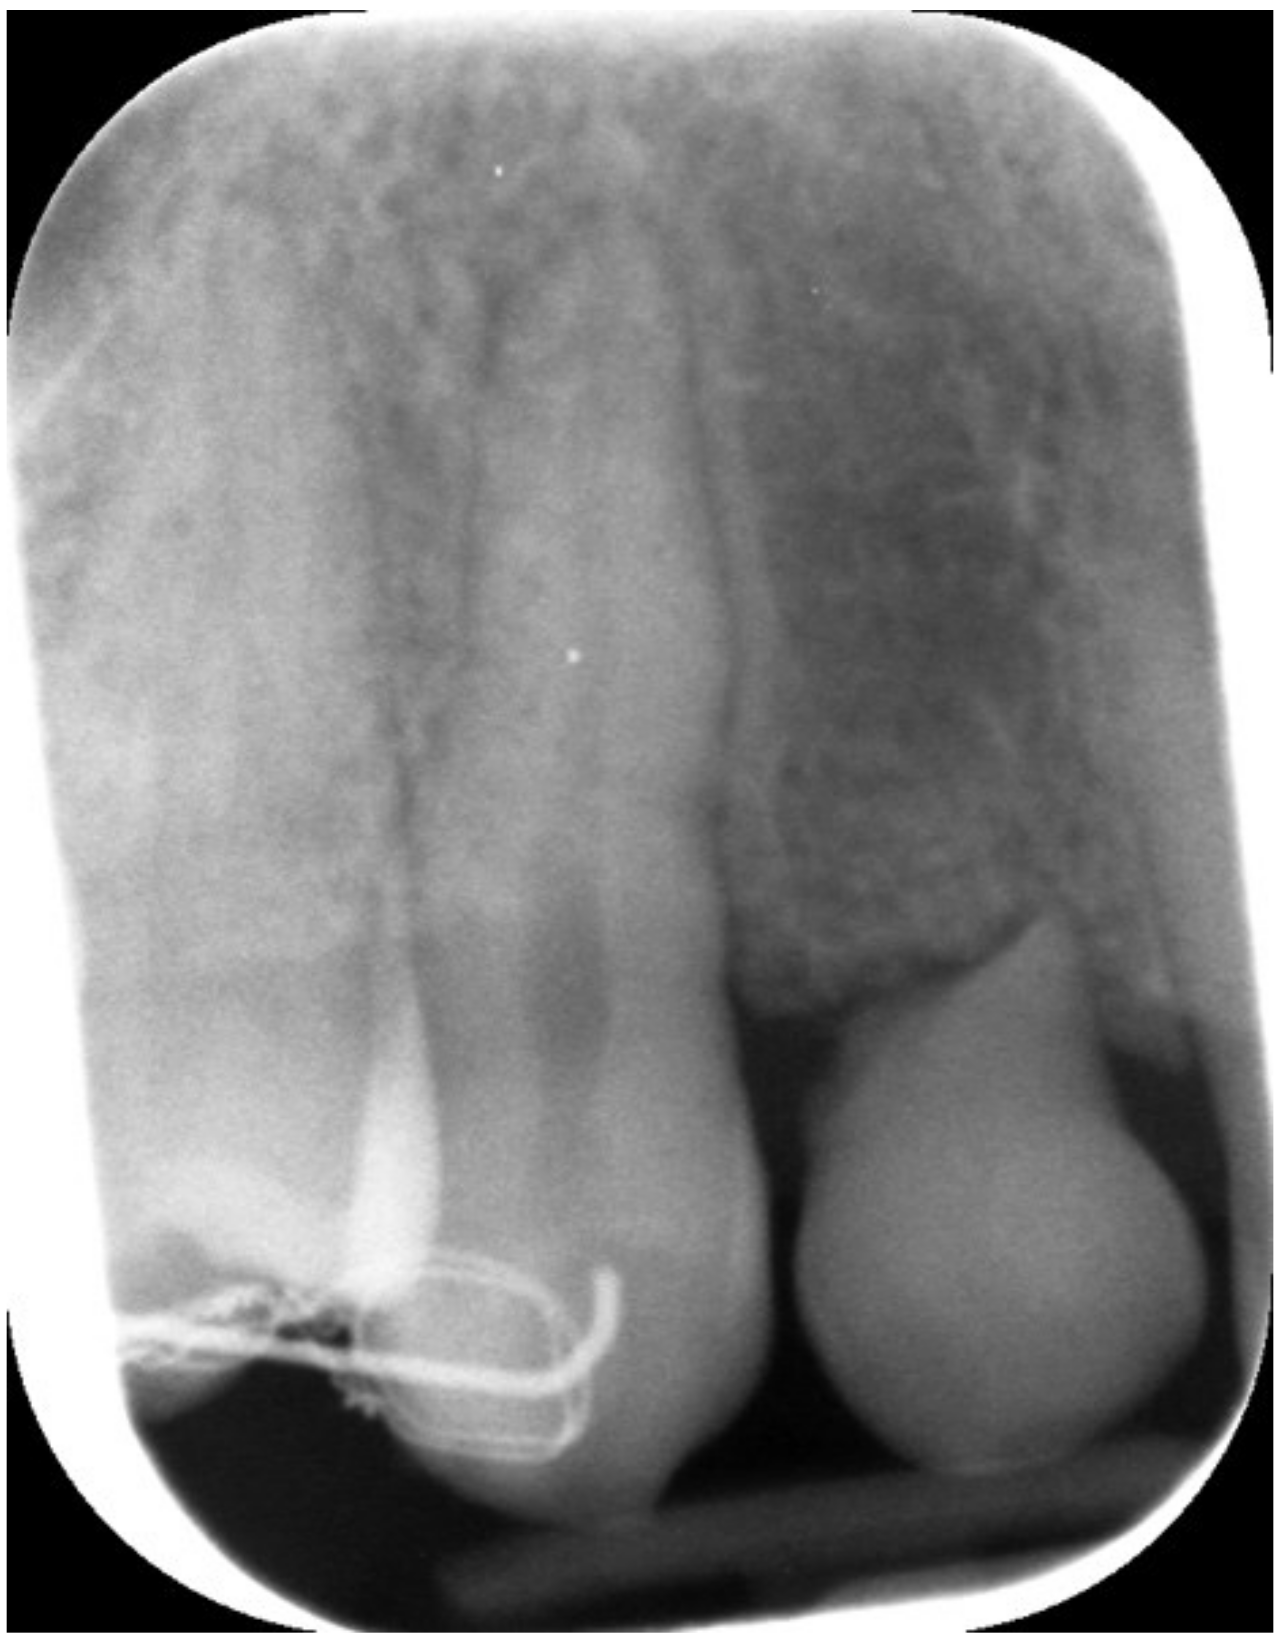

Figure 3.

Periapical X-ray showing deciduous canine.